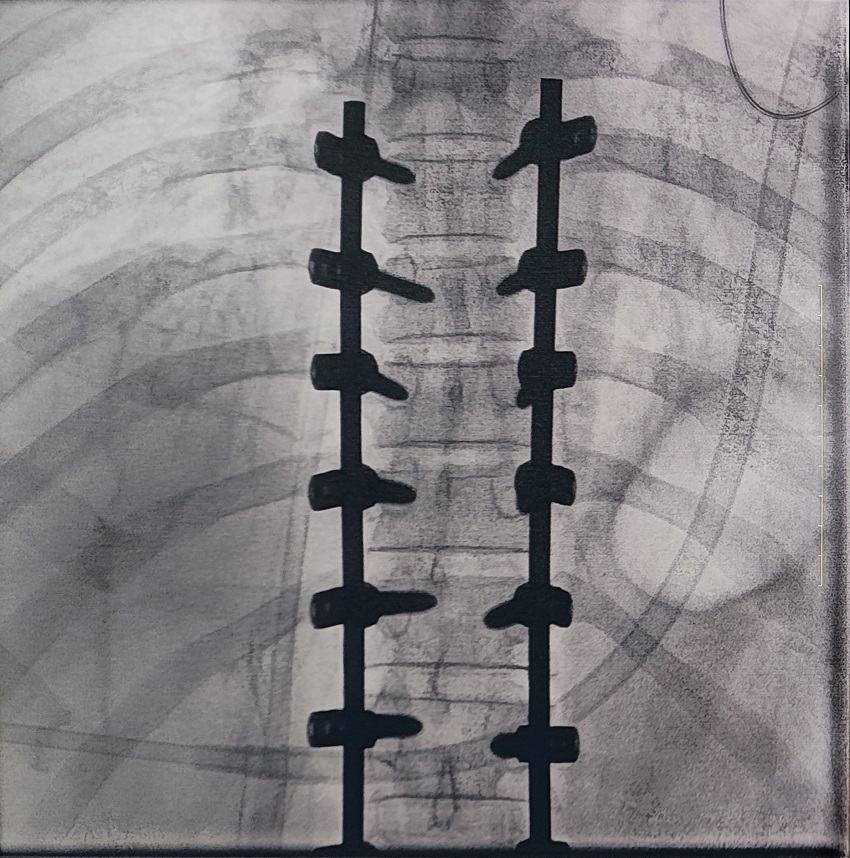

一場脊柱手術中,醫生需要拍攝跨越7個節段的脊柱影像,由于曝光的視野較大,常規視野的C形臂通常需要拍攝2-3次,普愛醫療大平板一體式C形臂30CM*30CM的“大視野”,輔助醫生一次性完成了7個節段的拍攝。最終,醫生在高清影像的輔助下完成了14枚螺釘的精準定位、置入。

骨科手術C臂機臨床圖像

大視野,不僅意味著醫生可以更快,獲取更全面的影像信息,做出精準判斷,無需多次拍攝定位,也顯著地降低了患者接受的輻射劑量,保護了患者的安全。